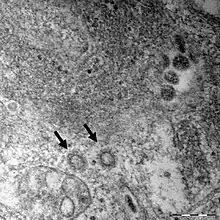

Micrograph of the SARS-CoV-2 virus particles